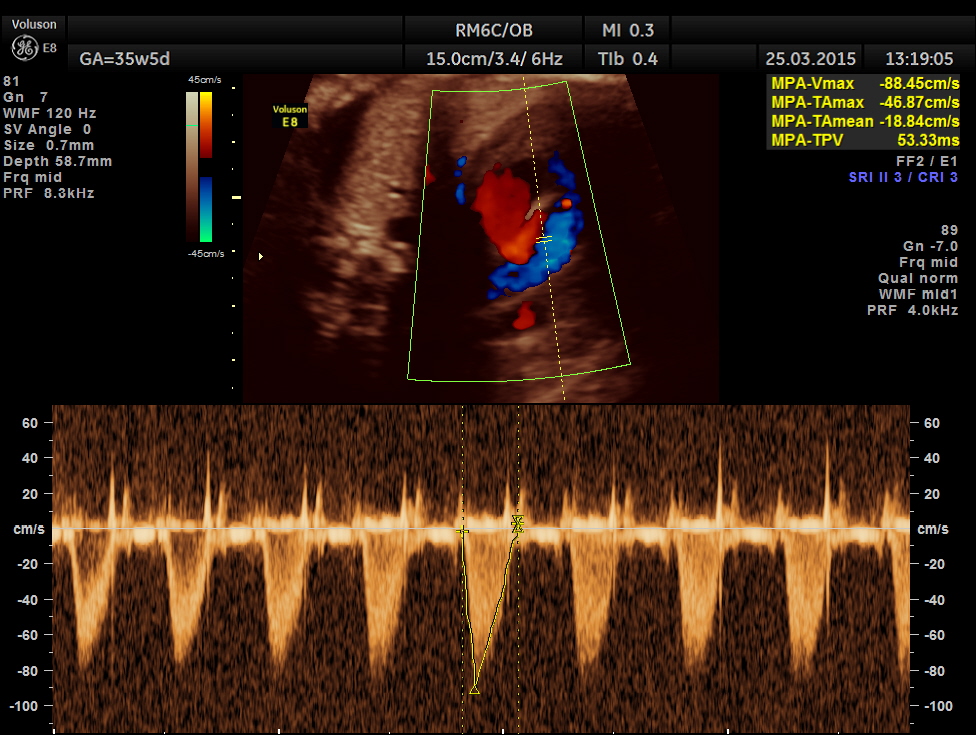

Mitral valve doppler flow.

Tricuspid doppler flow.

The artery coming out of left ventricle branches into two – suggestive of pulmonary artery.

The great artery arising from the LV branches into two suggestive of pulmonary artery.